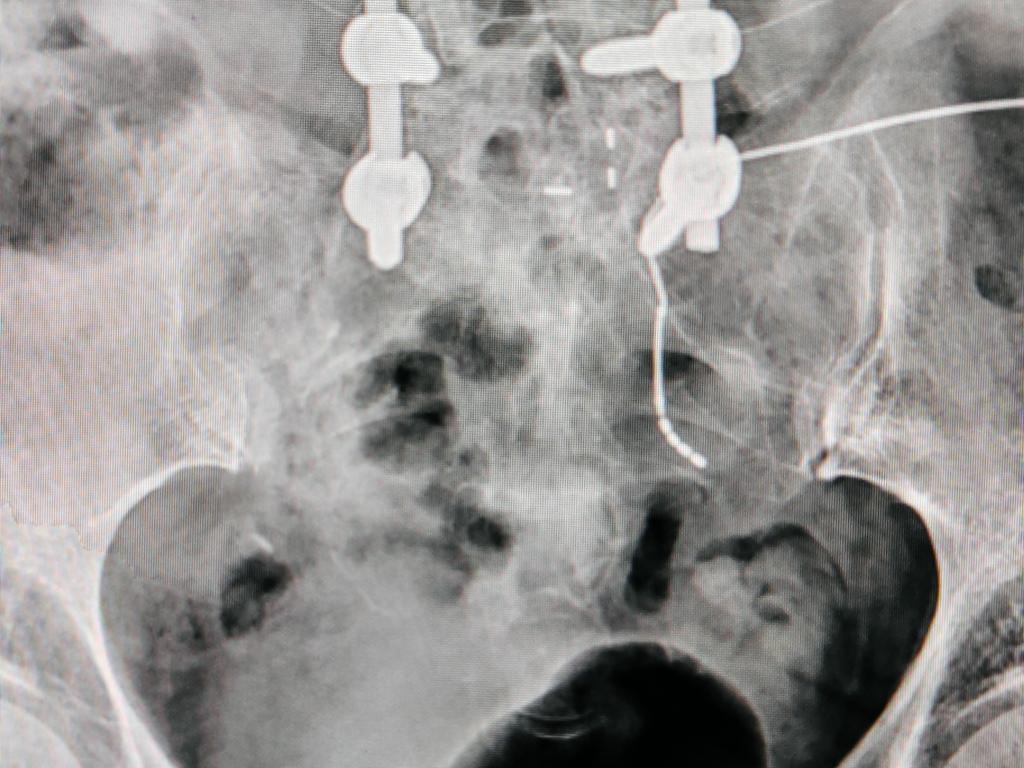

经术中超声辅助定位、术中测试,确认患者双侧S3神经感觉与运动应答均较差,左侧S2测试患者获得了“左侧臀部、大腿根部及肛门周边感觉良好应答、左侧足底跖屈反射刺激应答明确且无腓肠肌震颤、在增加脉宽后会阴部左侧区域感觉应答明确”,依据西安交大二附院“尿控与盆底修复”诊疗团队在完全脱离X线-B超辅助定位骶神经调控疗法个体化手术经验,术中确定选择患者左侧S2神经孔置入电极并确认深度并精准释放,术中最低测试电压0.5V,等待患者术后体验治疗24小时、完成X线电极定位复查,开始骶神经调控Stage1体验治疗。

临时刺激器连接并开机 SNM Stage1术中24小时X线复查